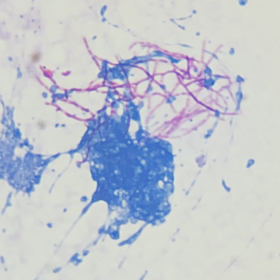

微生物实验室老师结合涂片及菌落形态,怀疑为诺卡菌,立即找到原始标本进行涂片革兰染色以及弱抗酸染色,涂片革兰染色镜检见大量“长丝状有直角分枝”的革兰阳性菌,见图3;弱抗酸染色见弱抗酸阳性菌,见图4。初步判断为诺卡菌。

图4 脓液涂片弱抗酸染色(1000×)